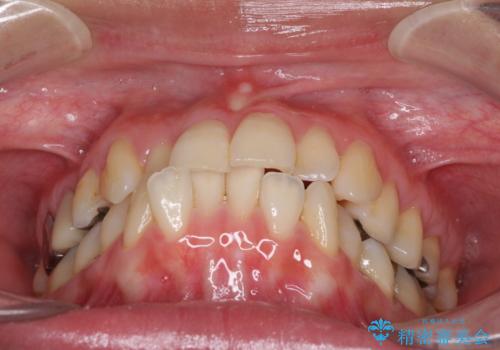

切端咬合をインビザライン矯正で解消

- 前歯のデコボコを気にして来院された患者様です。

上下前歯の先端同士が接触する切端咬合であったため、上顎は歯列を拡大し、下顎はIPR(歯と歯の間を削る)により叢生を解消しながら歯列を小さくすることとしました。

切端咬合はスムーズに解消され、前歯の負担を軽減させることができました。